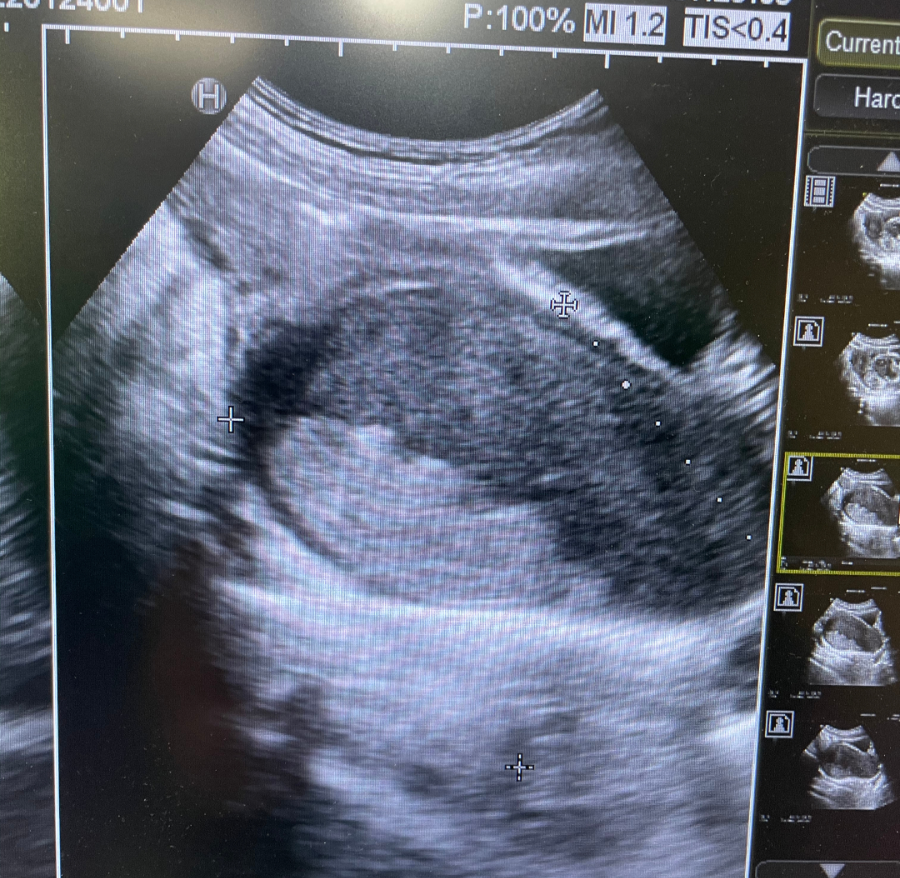

2022年1月24日晚上21點,我院婦科董徐男主任團隊聯手功能(néng)科主任楊靜在B超實施監察下爲小美進(jìn)行無損傷處女膜宮腔鏡下陰道(dào)斜隔電切術,手術順利完成(chéng),效果立竿見影,小美當即感到腹痛症狀明顯得到緩解。

(2)在超聲監護下,用宮腔電切鏡的針狀電極電切開(kāi)陰道(dào)斜隔,解除斜隔後(hòu)的經(jīng)血引流問題。